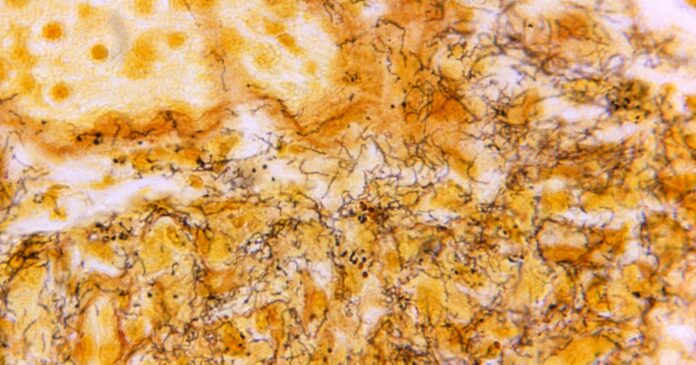

Syphilis is a bacterial disease that surfaces as genital sores but can ultimately lead to severe symptoms and death if left untreated.